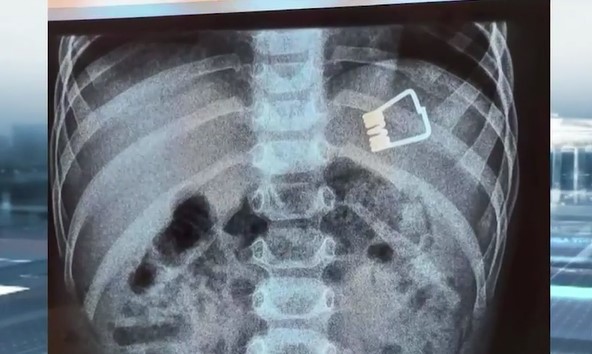

Λήμνος: Δίχρονο αγοράκι κατάπιε μανταλάκι – Πώς το έσωσαν οι γιατροί